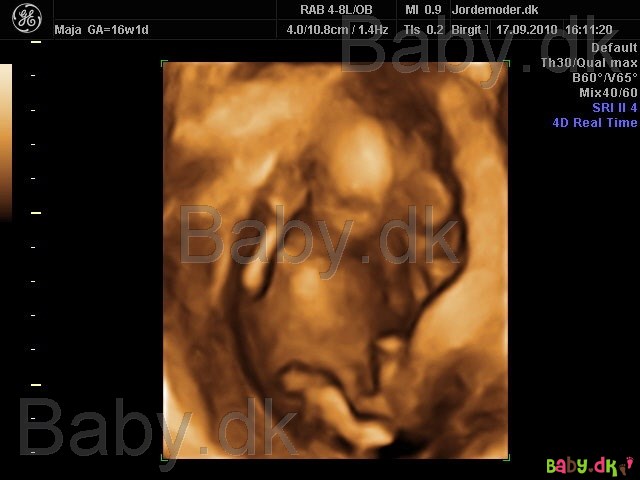

Det her er dog fra Kønsscanning 14+ men man kan da se noget!

Vedhæftede fotos (klik for at se i fuld størrelse)